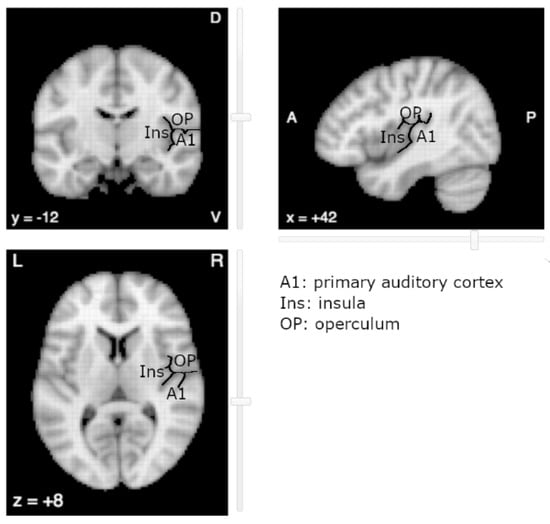

The near-complete absence of literature on OpP with regard to tinnitus is surprising. One explanation relates to its vicinity with the primary auditory cortex (A1) (Figure 1). Due to the spatial smoothing and the spatial normalization of MR images, the fMRI activations in OpP could be mistakenly reported as activations of the primary auditory cortex or of the posterior insular cortex (post-Ins). Indeed, located on the opposite banks of the lateral sulcus, OpP, post-Ins and A1 are close to one another, OpP being more anterior and superior and post-Ins more medial and anterior than A1, respectively. In the human cortex, regions that lie on opposite banks of a main sulcus generally present mirror organization, with mirror somatotopy around the central sulcus for primary motor on the anterior side and primary sensory on the posterior side, with mirror retinotopy around the calcarine sulcus with inferior part of a hemifield above the sulcus and the superior part below the sulcus. Up to now, no such mirror tonotopy has been observed in human areas opposite to A1. To our knowledge, a single study reported a tonotopic organization in the insula, but in a rodent model [].

Figure 1.

The auditory area (A1), parietal operculum (OP) and posterior Insula (Ins) lie on opposite banks of the lateral sulcus (underlined in black). Image derived from neurosynth.org (last accessed on 1 September 2021).